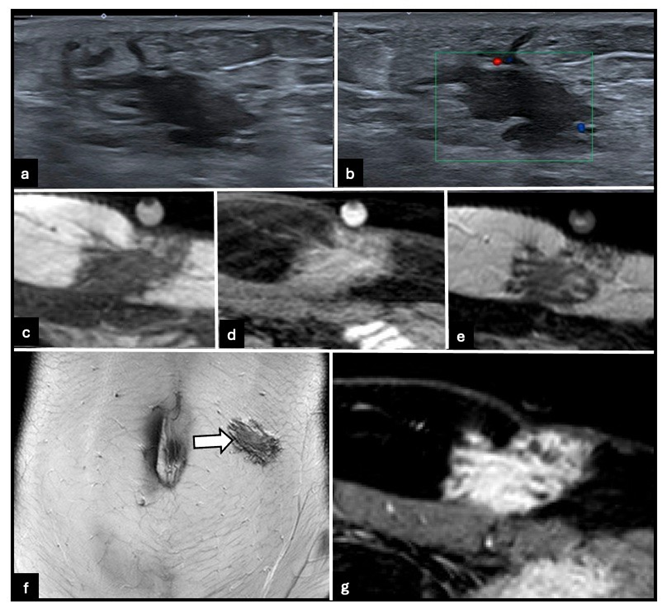

Ultrasound is often the first-line imaging modality but remains nonspecific. Lesions usually appear as ill-defined hypo- to isoechoic masses with variable vascularity on color Doppler imaging. Cystic components may be present, and lesion appearance can fluctuate throughout the menstrual cycle. Fine-needle aspiration often yields insufficient or non-diagnostic material due to the fibrotic content of the lesions. Core biopsy may be considered, but puncture tracts should be excised during subsequent surgery to prevent recurrence [3].

MRI is the reference standard for evaluating abdominal wall and intramuscular endometriosis. Imaging features vary according to lesion composition. Predominantly fibrous lesions exhibit low to intermediate signal intensity on T2-weighted images, often with ill-defined margins and infiltrative growth patterns (Figure 1). Intramuscular cystic lesions may be well-circumscribed, occasionally resembling ectopic ovarian endometriomas (Figure 2). Infiltrative intramuscular lesions with hemorrhagic microcysts present as punctate or confluent hyperintense foci on fatsuppressed T1-weighted images (Figure 3). Overall, lesions can be iso- to hyperintense relative to muscle on T2-weighted images, with focal T1 hyperintensity reflecting hemorrhagic components, a feature highly suggestive of endometriosis. [3,5] After gadolinium administration, lesions usually demonstrate moderate to marked, often heterogeneous, enhancement. Lesions may appear nodular, spiculated, or retractile and can infiltrate adjacent muscular layers, including the rectus abdominis or oblique muscles. Diffusionweighted imaging often demonstrates intermediate diffusion restriction, with reported apparent diffusion coefficient (ADC) values around 0.93 × 10⁻³ mm²/s. [5] MRI also permits accurate delineation of lesion extent through the abdominal wall layers and facilitates detection of concurrent pelvic disease, which is essential for comprehensive surgical planning [3,5].

Figure 1: 33-year-old woman with predominantly fibrous hypodermic abdominal wall endometriosis on the left side. (a) B-mode ultrasound image shows an ill-defined hypodermic lesion of the left abdominal wall. (b) Color Doppler ultrasound image shows minimal vascularity. (c) Axial T1-weighted MRI image demonstrates low signal intensity. (d) Axial fat-suppressed T1-weighted MRI image shows foci of hyperintensity. (e) Axial and (f) coronal T2-weighted MRI images demonstrate low to intermediate signal intensity (arrow), consistent with a predominantly fibrous infiltrative lesion. (g) Axial contrast-enhanced 3D T1-weighted GRE MRI image shows moderate heterogeneous enhancement.